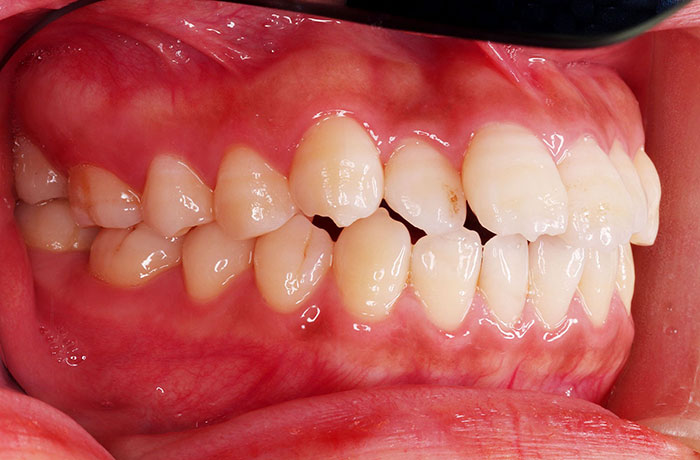

治療前

before

患者の症状 上顎前歯の前突、開咬、下顎前歯部の空隙

治療方法 非抜歯で、マウスピース型カスタムメイド矯正歯科装置による矯正

上顎臼歯の遠心移動とIPR(歯間隣接面を削合)しました。

治療結果 上顎前歯の前突、開咬が改善されました。